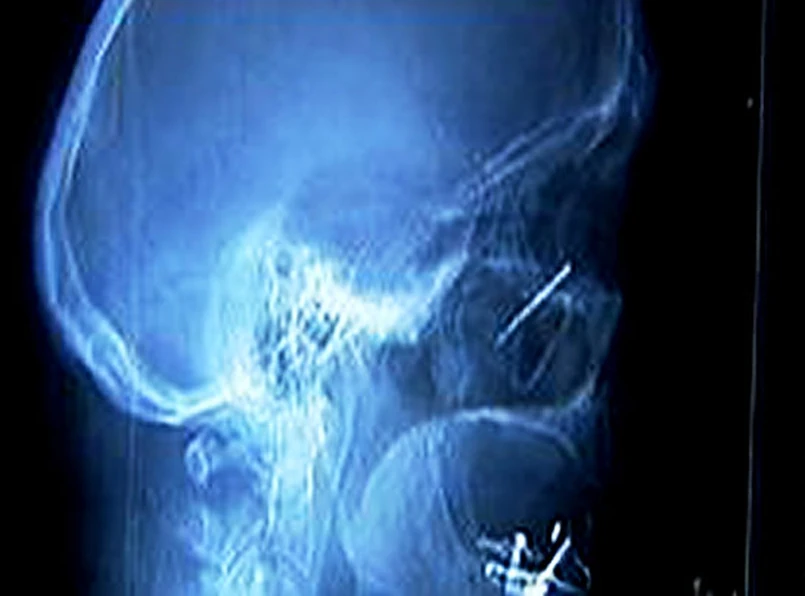

Przedmiot wykryli lekarze w czasie prześwietlenia za pomocą rezonansu magnetycznego. Na chwilę przerwali badanie, aby przekazać pacjentowi, że ma w gardle coś metalowego.

Chwilę po tym Sanchez wykaszlał gwoździa. Lekarz nie wykluczał, że przedmiot mógł tkwić w gardle pacjenta nawet 30 lat. Działanie rezonansu magnetycznego prawdopodobnie zmieniło jego położenie i pozwoliło się go pozbyć.